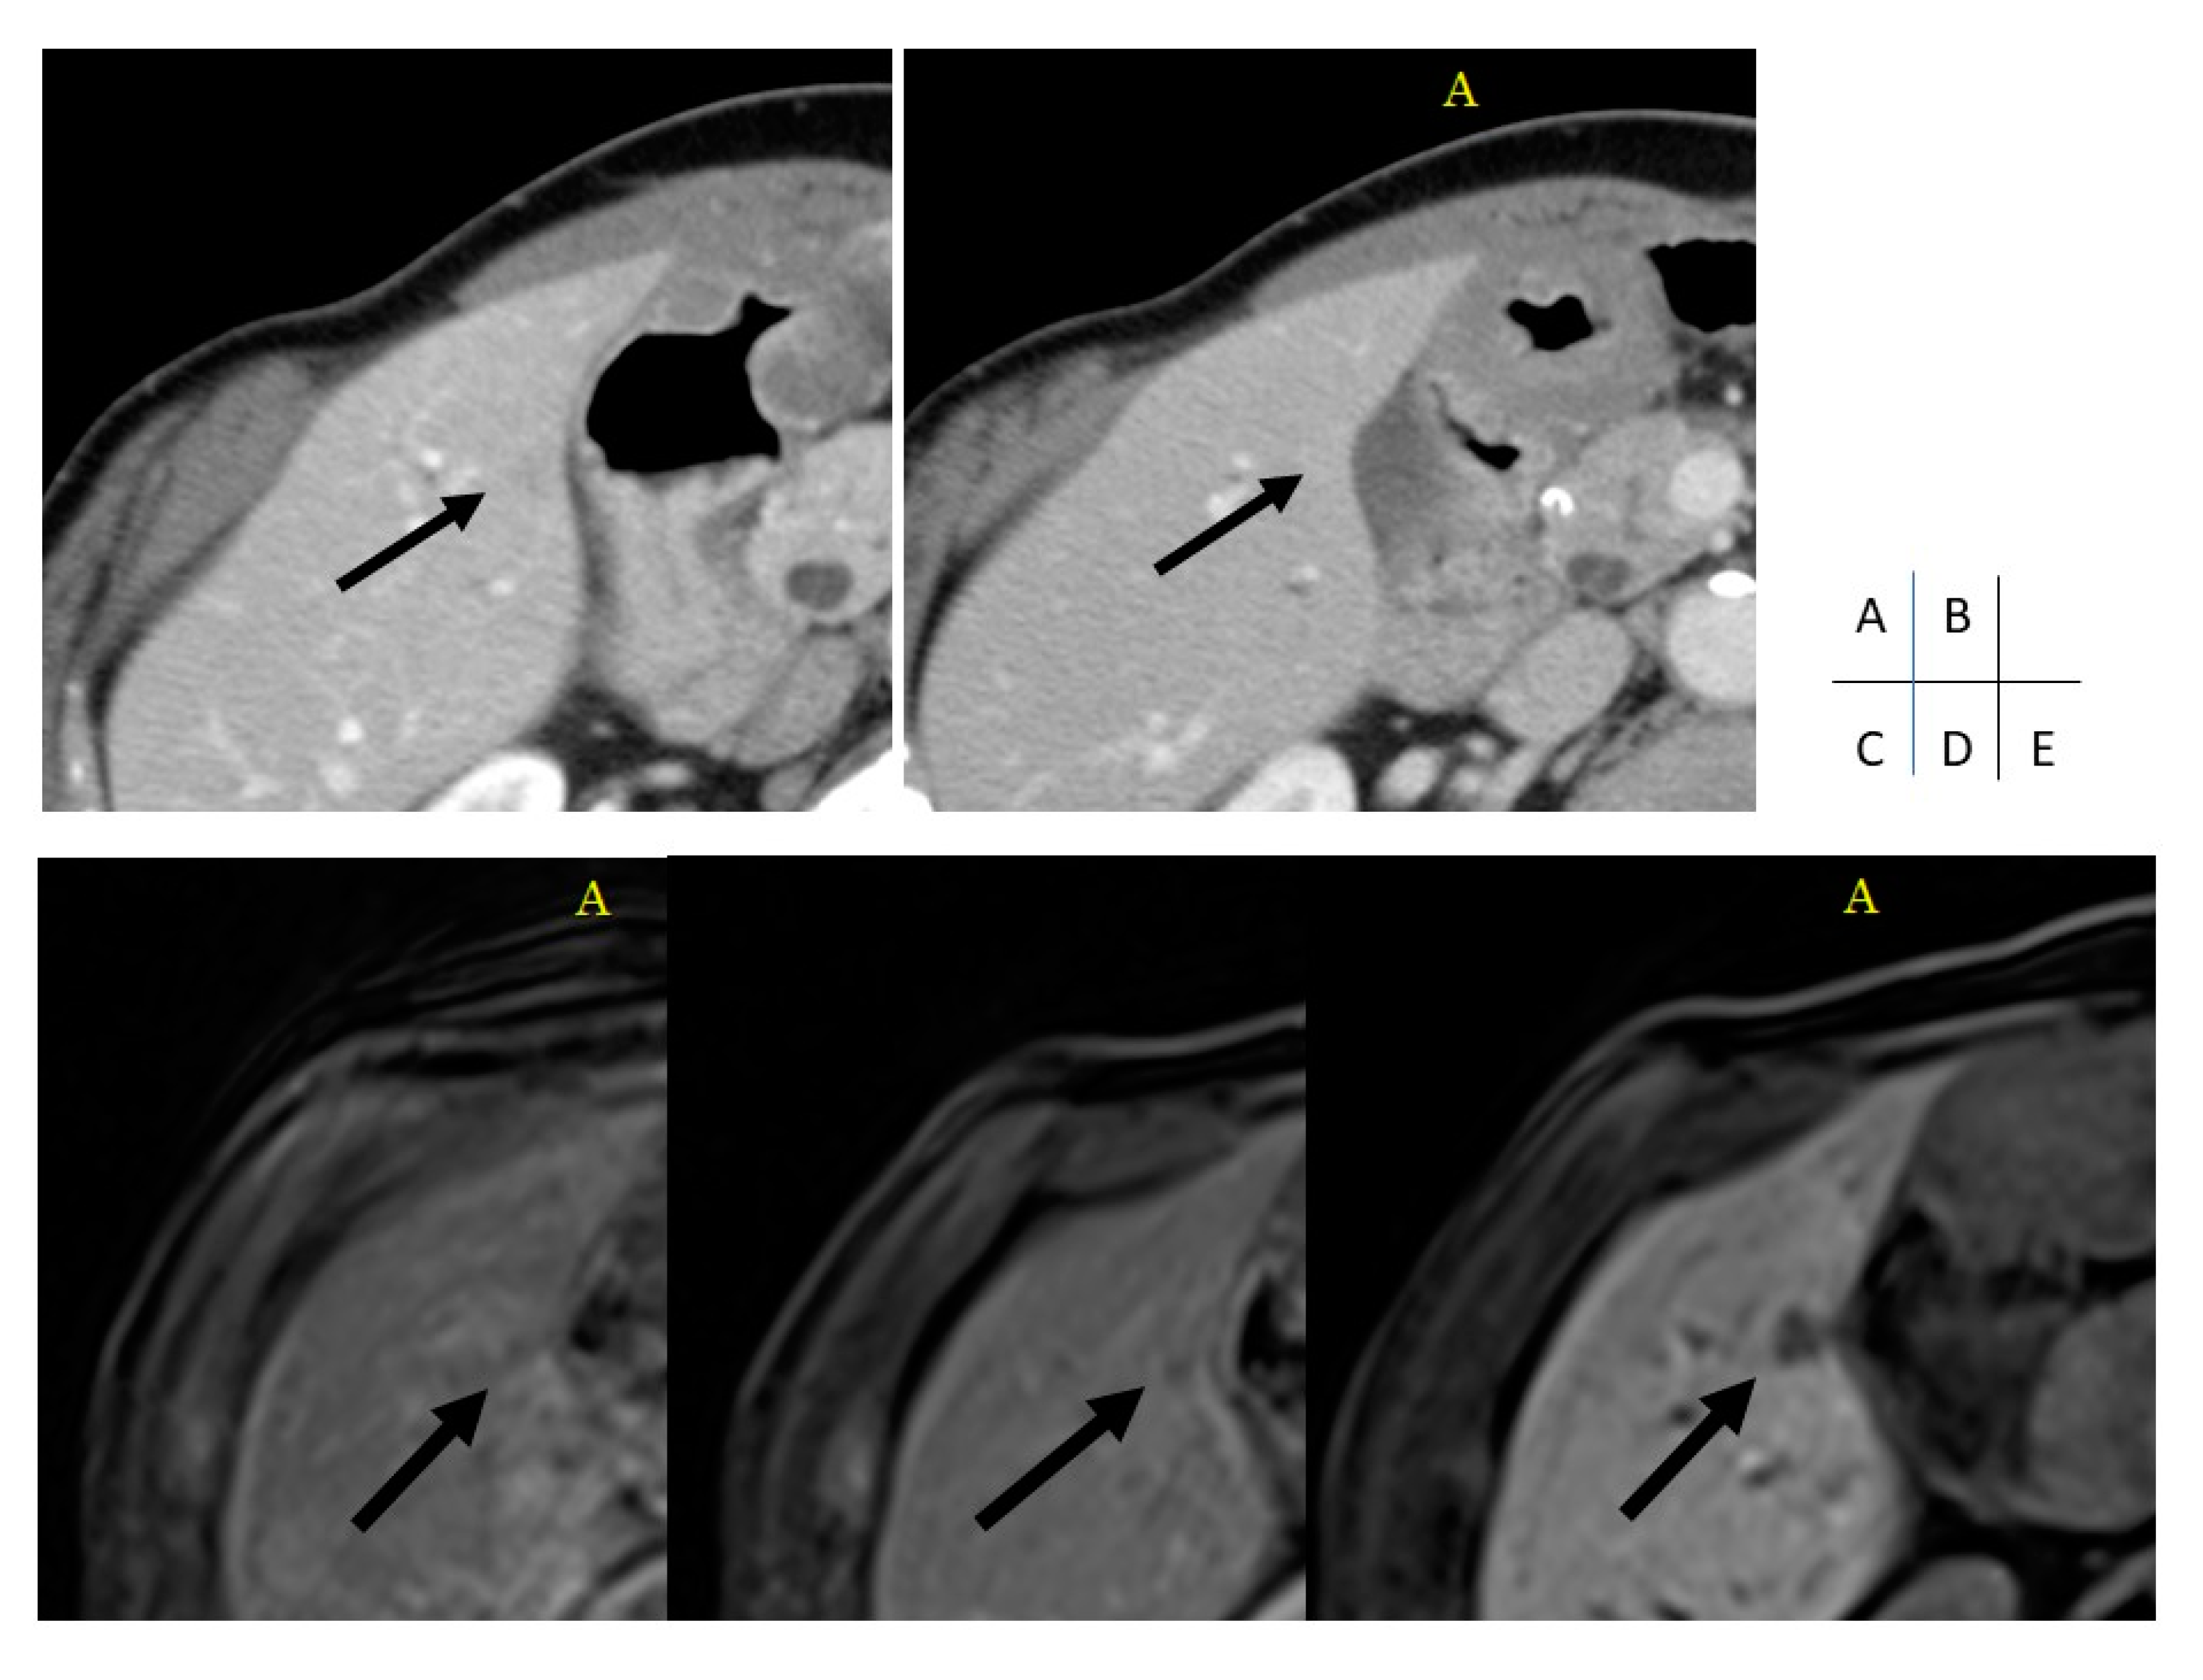

Assessment of Liver Metastases Using CT and MRI Scans in Patients with Pancreatic Ductal Adenocarcinoma: Effects of Observer Experience on Diagnostic Accuracy